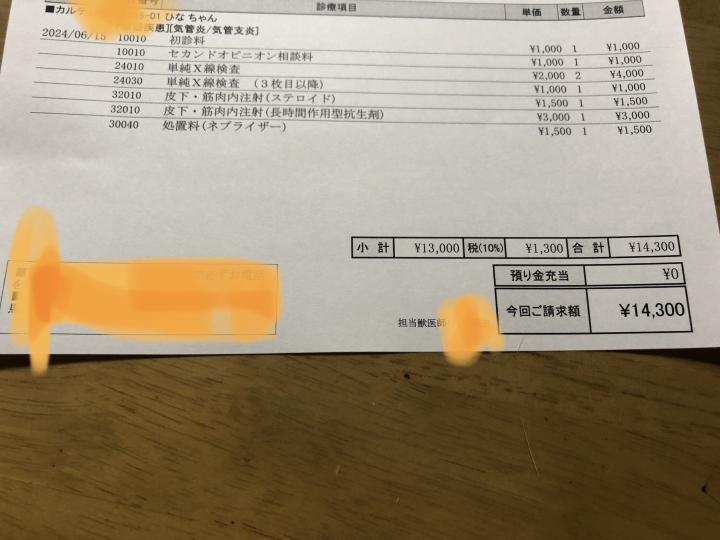

会計メモ